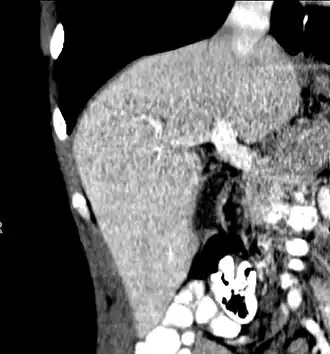

Left lobe liver tumor

The liver is a vital organ and supports almost every other organ in the body. Because of its strategic location and multidimensional functions, the liver is prone to many diseases.[58] The bare area of the liver is a site that is vulnerable to the passing of infection from the abdominal cavity to the thoracic cavity. Liver diseases may be diagnosed by liver function tests–blood tests that can identify various markers. For example, acute-phase reactants are produced by the liver in response to injury or inflammation.

After resection of left lobe liver tumor

Liver transplantation is the only option for those with irreversible liver failure. Most transplants are done for chronic liver diseases leading to cirrhosis, such as chronic hepatitis C, alcoholism, and autoimmune hepatitis. Less commonly, liver transplantation is done for fulminant hepatic failure, in which liver failure occurs rapidly over a period of days or weeks.